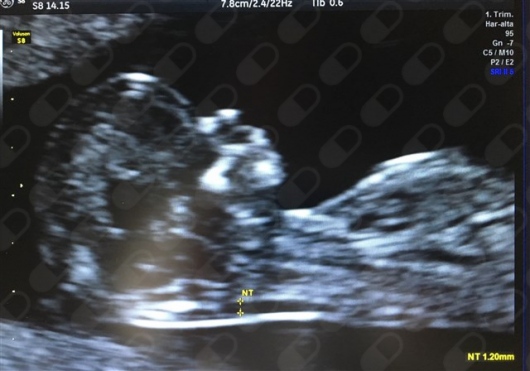

• Ultrasonido para marcadores de Síndrome de Down

$1,500

La evaluación en primer trimestre puede llegar a detectar hasta en un 95% de los casos marcadores de enfermedades cromosómicas, principalmente Síndrome Down. El test no invasivo consiste en: - Realizar un ultrasonido nivel II o avanzado en las semanas 11-13.6 semanas donde se mide la translucencia nucal. - Muestra de sangre materna para medición de marcadores bioquímicos (recomendable realizarlo, sin embargo se puede individualizar cada caso). Los elementos antes mencionados en combinación con la edad de la mamá y la medición del bebé nos arroja un riesgo, el cual puede ser bajo, intermedio o alto, siendo pieza fundamental en la atención prenatal para brindar un asesoramiento adecuado.